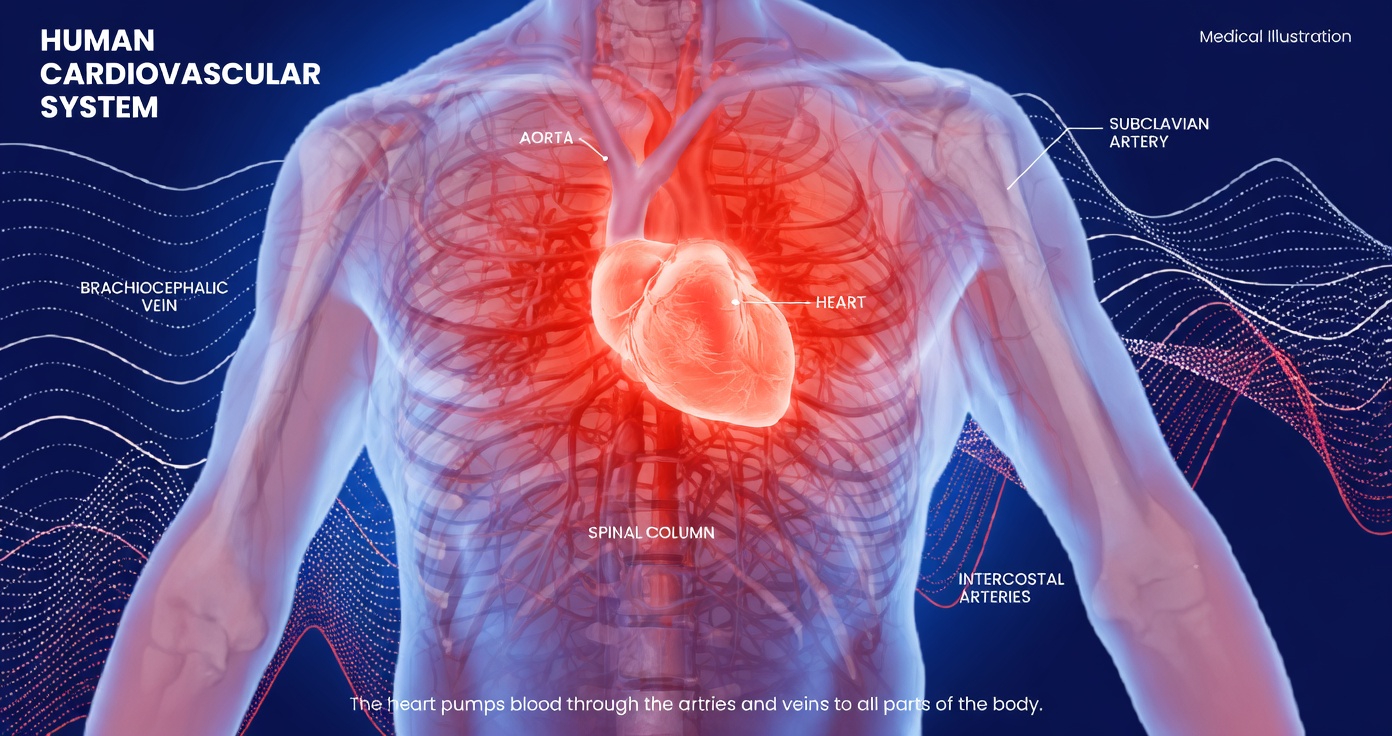

How Amlodipine Works

Amlodipine is a calcium channel blocker. It helps relax and widen blood vessels, making it easier for blood to circulate and helping keep blood pressure in a healthier range. It is also commonly used for certain types of angina.

According to sources such as the FDA label, Mayo Clinic, and WebMD, amlodipine is generally considered well tolerated. Still, like all medications, it may cause side effects in some people. In many cases, these reactions are mild and improve during the first few weeks as the body adapts.